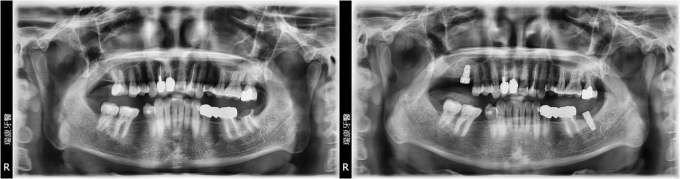

病患呂小姐,65年次,家庭主婦

- 主訴:右下牙橋搖晃嚴重,想重建

- 治療計劃: 拔除嚴重牙周病之牙齒,等待三個月癒合期, 安排精密3D電腦斷層評估後,進行人工植牙, 三個月後接出假牙基座印模製作正式假牙!

實例照片僅為資訊介紹及分享,效果可能因個人體質及保養方式不同而有所差異。